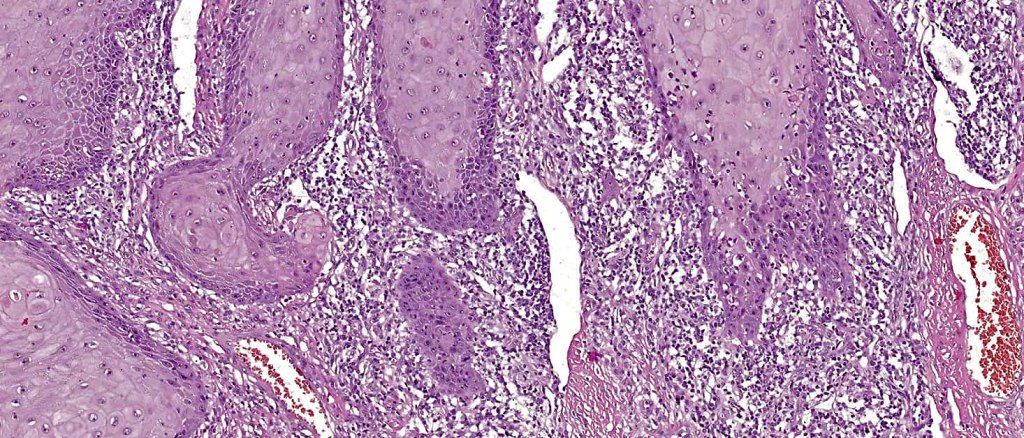

Histoloigcal features

•Often massive hyperkeratosis

•Epidermal verrucous hyperplasia

•Deeply penetrating bulbous processes with a pushing rather than infiltrating lower border

•Well differentiated epithelium characteristically having a ground glass appearance

•Marked tumor necrosis

•Intraepithelial abscesses

•Basally located mitoses